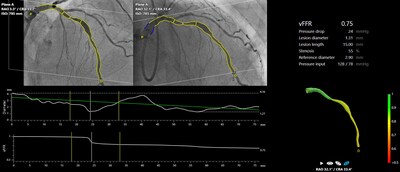

Schnittstelle von CAAS vFFR für die Echtzeit-Bewertung der Signifikanz von Läsionen im Kathlab.

FAST III war eine vom Prüfarzt initiierte, offene, multizentrische, randomisierte Studie, in der eine vFFR-geführte mit einer FFR-geführten Koronarrevaskularisation bei 2235 Patienten mit intermediären Koronarläsionen (definiert als 30-80%ige Stenose durch visuelle Beurteilung oder QCA) verglichen wurde. Intermediäre Läsionen wurden physiologisch anhand von vFFR oder FFR auf der Tischseite beurteilt und behandelt, wenn vFFR oder FFR ≤0,80 waren. Der primäre Endpunkt war ein Kompositum aus allen Todesursachen, einem Myokardinfarkt oder einer Revaskularisierung 1 Jahr nach der Randomisierung.